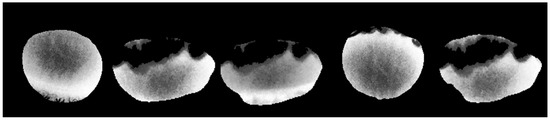

To evaluate the performance of our eyelash removal method, we applied it to IR images from five different corneas, as shown in Figure 3. The variation in the outer contours is due to differences in individual eye shapes. The primary purpose of this figure is to showcase the successful removal of eyelashes, which appear as black regions, rather than to compare corneal shapes. For better interpretability, we note that in these infrared images, darker areas indicate cooler temperatures, while brighter areas correspond to warmer regions.

Figure 3. Sample IR frames of the cornea ROI from five different eyes, demonstrating the effectiveness of the eyelash removal method. The black areas represent the removed eyelashes, ensuring that only the corneal surface is analyzed for temperature measurement. In these IR images, darker areas correspond to cooler regions, while brighter areas indicate warmer regions. The ocular surface temperature typically ranges between 32 °C and 36 °C, depending on environmental conditions and physiological factors.